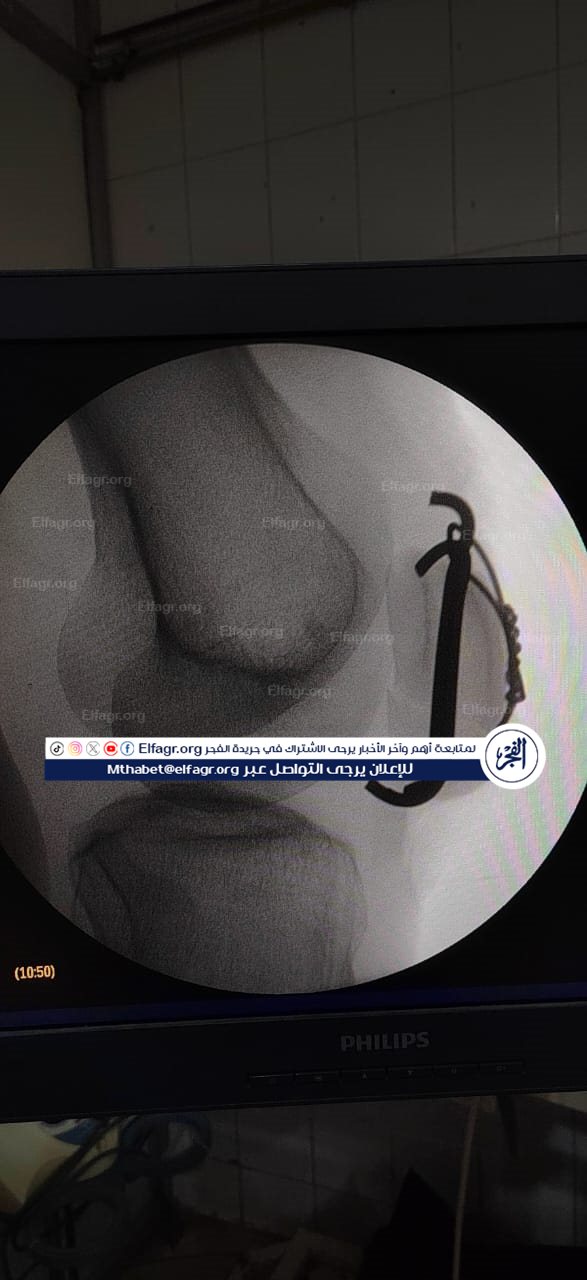

شملت العمليات تركيب كويرات بالرضفة اليسرى لمريض، وكذلك تركيب مسمار نخاعي بالفخذ الأيسر لمريض آخر، حيث تمت العمليتان بدقة عالية وباستخدام تقنيات حديثة ساهمت في تحقيق النتائج المرجوة.

جانب من الجراحة